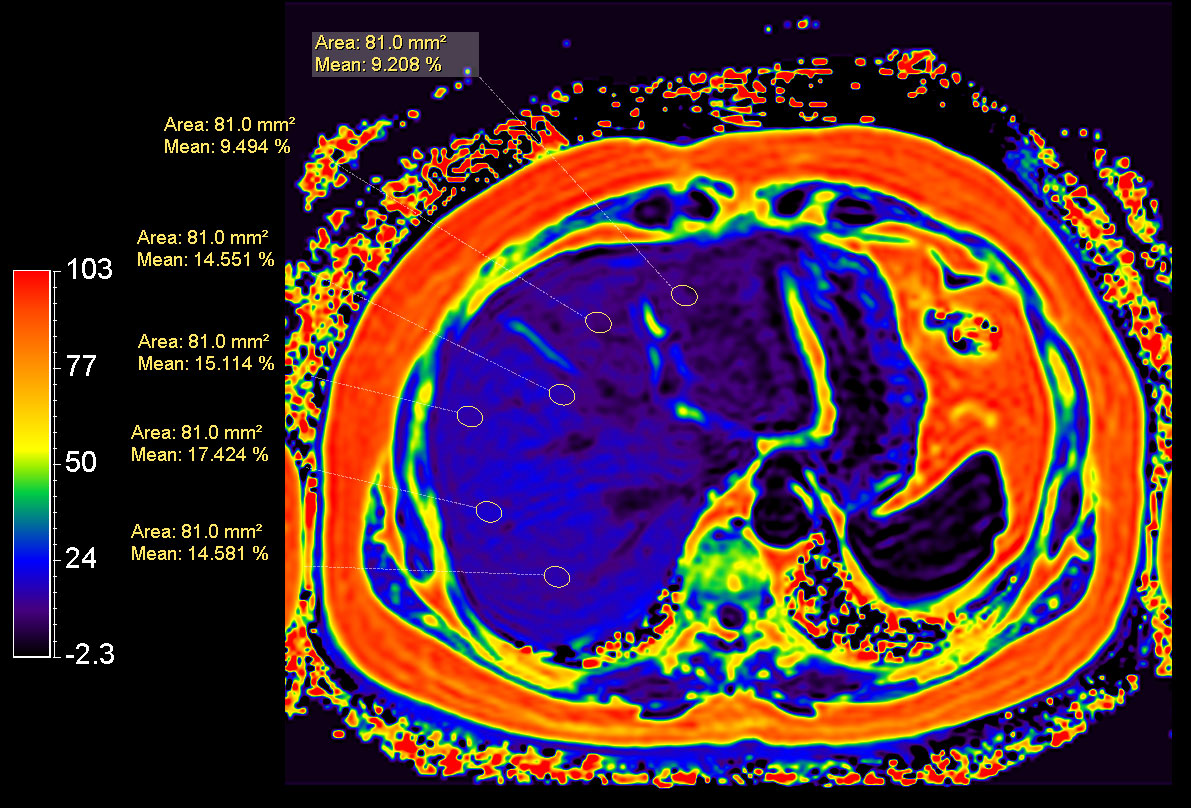

mDIXON Quant (Fat Fraction)